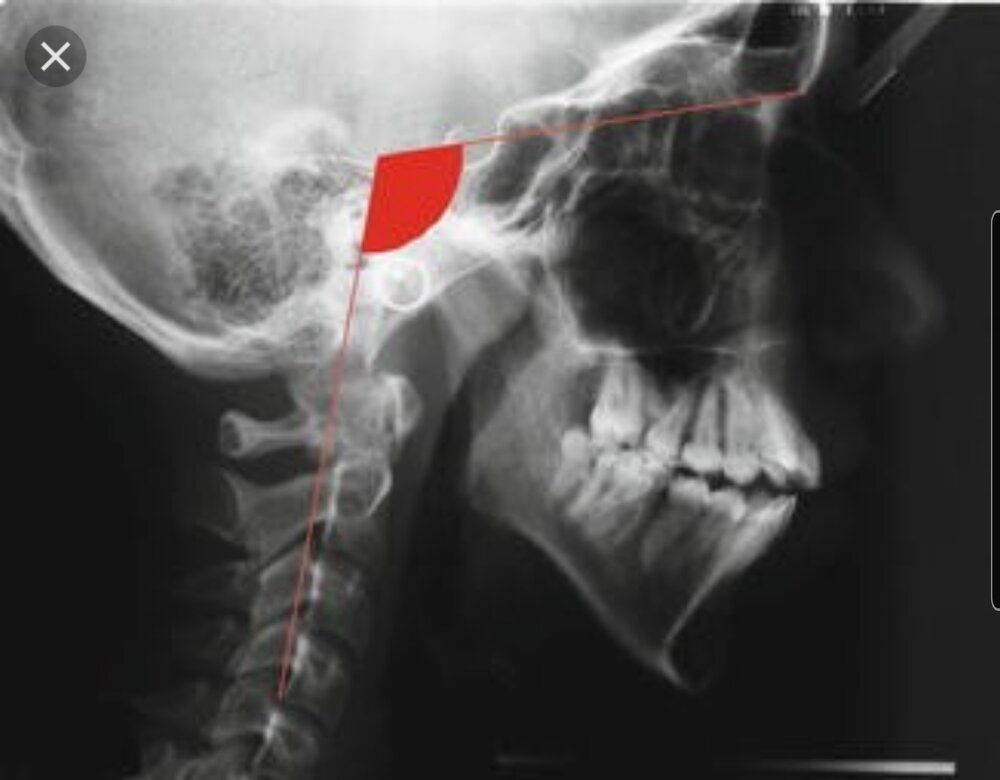

But it's weird he has all teeth in no crooked teeth no sleep apnea no extractions and doesnt have long midface like this:He has same side as I have. Maxilla isn´t forward growth enought, short mandible locked back far far away to the neck.

View attachment 454727

I'd have to see your skull scan to see but I guess your mandible is looking somewhat like this:I mouthbreathed as a child that’s all I know jfl

It’s pretty much like that yeahI'd have to see your skull scan to see but I guess your mandible is looking somewhat like this:

View attachment 454741